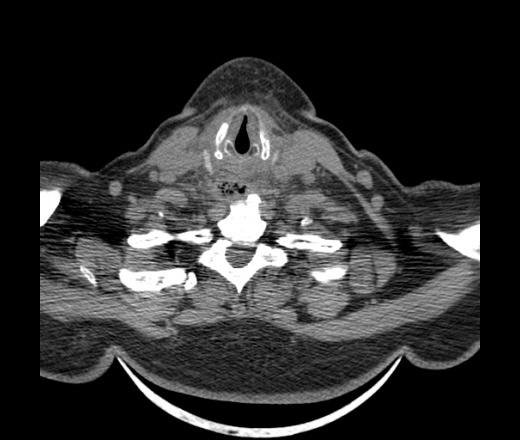

Женщина поступила в х/о спустя 4 дня после того как при употреблении карася подавилась костью.

Наличие газа в средостении на протяжении тел С2-С6 (медиастинальна эмфизема); рыбная кость на уровне тела С6.

При всем уважении, но говорить о медиастинальной эмфиземе, оценивая мягкие ткани шеи, как-то слишком резко. На мой взгляд, это ретрофарингеальное пространство.

Эвакуировали почти 100мл гноя. Но кость не смогли найти. Думаю что она даст дальнейшее ослоднение. Эндоскопически за черпалонадгортаной звязкой не смогли зайти в пищевод, все мягкие ткани отечные, просвет пищевода сдавлен. По всей видимости параэзофагеальная клетчака тоже задействована. Эмпиема, если ее можно так назвать, незнаю как правильно дошла до уровня яремной вырезки. Чем закончиться напишу. Ждем медиастинита.

Согласен с Вами; конечно, наличие газа в клетчатке ретрофарингеального пространства (затмение с опечаткой..). К сожалению, процесс "продвигается" к медиастиниту. Но почему никто, не отмечает наличие рыб. кости; или это для Всех очевидно?

Кость то мы сразу выявили, размеры где то 17*2мм, но ее так и не получается найти в этой каше